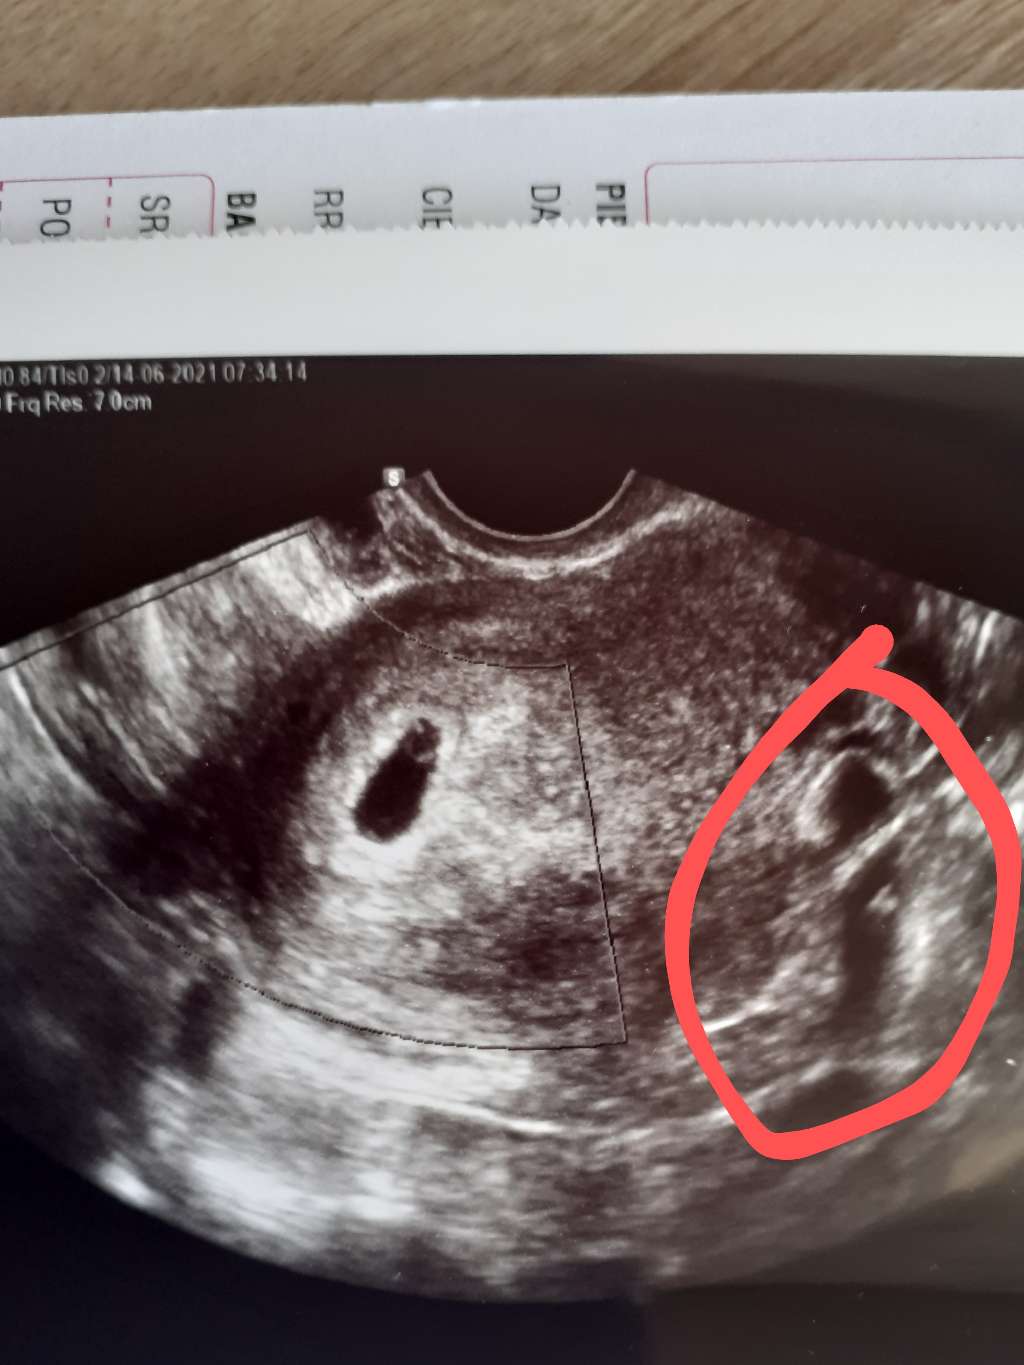

Dziewczyny mam pytanie

Powiedzcie mi co to może być ta druga plamka?

Lekarz nic nie mówił w sumie

a Ja ją zauważyłam dopiero teraz, ponad tydzień po wizycie

W sumie do tej pory skupiałam się tylko na pęcherzyku , ale zastanawia mnie to

Na pewno zapytam lekarza, ale wizyta 5 lipca